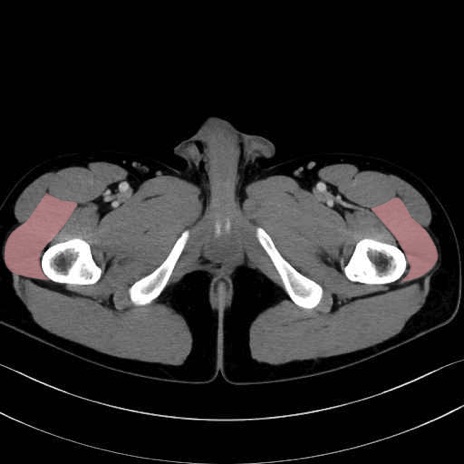

外側広筋(vastus lateralis) のCT画像の解剖

外側広筋 (Vastus lateralis)